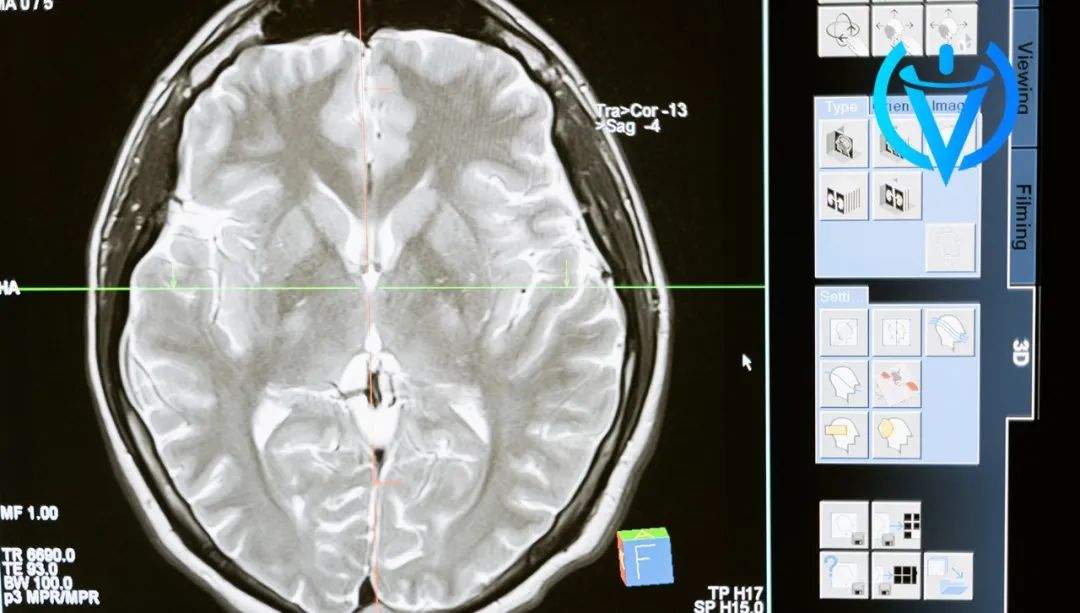

(图片来源:互联网)